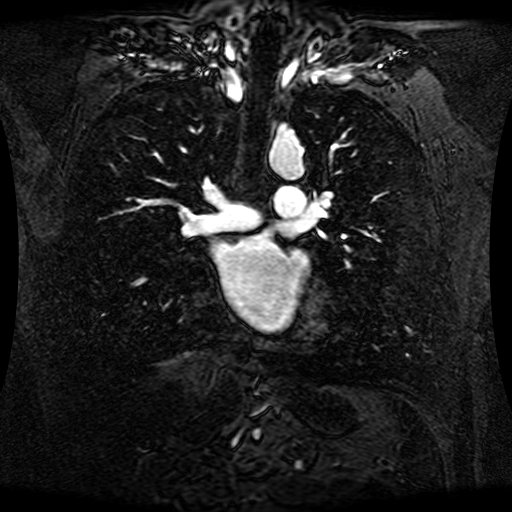

Data Description

These magnetic resonance angiography (MRA) images show coronal slices acquired from consecutive anteroposterior positions within the torso. The study was performed on a 1.5T General Electric (GE) Signa imaging system with gadolinium-contrast-enhancement for visualization of the cardiopulmonary vasculature. The pulse sequence used was a 3D time-of-flight fast spoiled gradient recalled acquisition in steady state (FSPGR, TR=6.3, TE=1.4, NEX=1, FOV = 40cm, slice thickness = 1.2mm).

This sample image contains 76 frames. It is available in DICOM format (E1154S7I.dcm), as an animated GIF (E1154S7I.gif), as .ogg, .mp4, .webm, and .swf animations (one of which is shown above), or as individual PNG-format frames (see below).